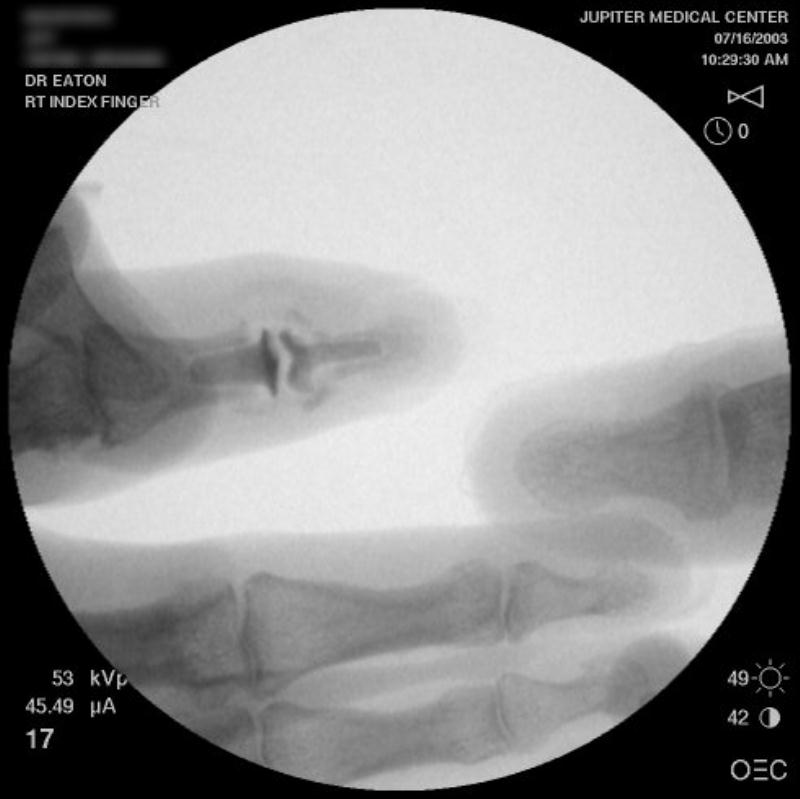

Intraoperative fluoroscopy.

Second case.

This patient had previous experience with both DIP fusion and PIP arthroplasty.

Ring finger DIP joint of the opposite hand.

Intraoperative fluoroscopy using the same technique as above. The trial spacers: